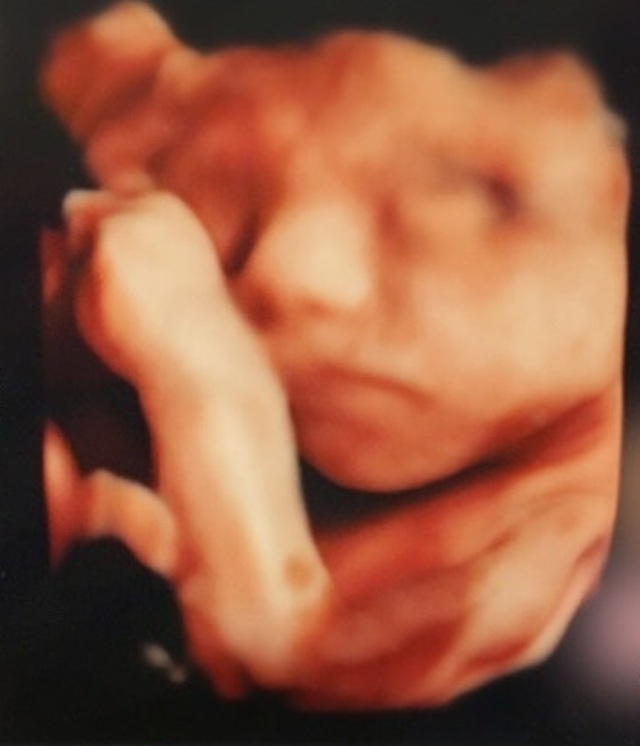

27週2日(27w2d・男の子)|maaa1261 さん(26歳)

エコー写真撮影時のエピソード:

いつも健診に行っている病院では2Dエコーしか対応しておらず、何件も問い合わせてやっと見つけた少し離れた病院で記念に4Dエコーを撮ってもらいました!赤ちゃんの顔が見れて、もうすぐ8ヶ月になり、エコーのおかげでやっと実感がわいてきたような感じがしました!